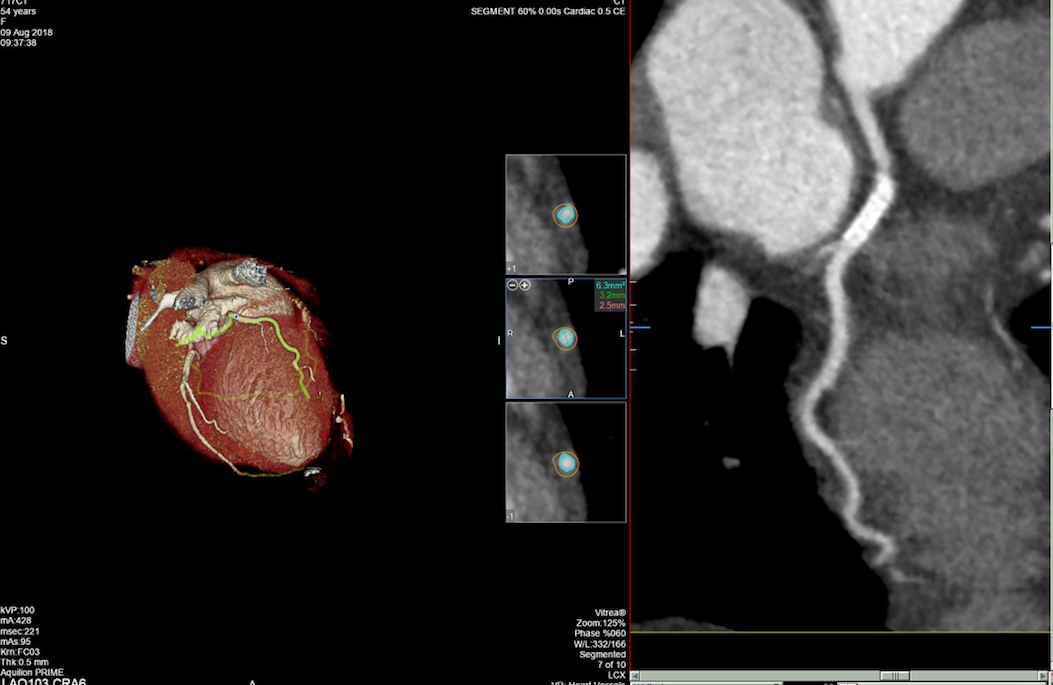

- MSCT koronarografija (prikaz krvnih žila srca CT-om, bez neugodnosti i komplikacija koje nosi klasična koronarografija), u saradnji s Poliklinkom dr.Al-Tawil